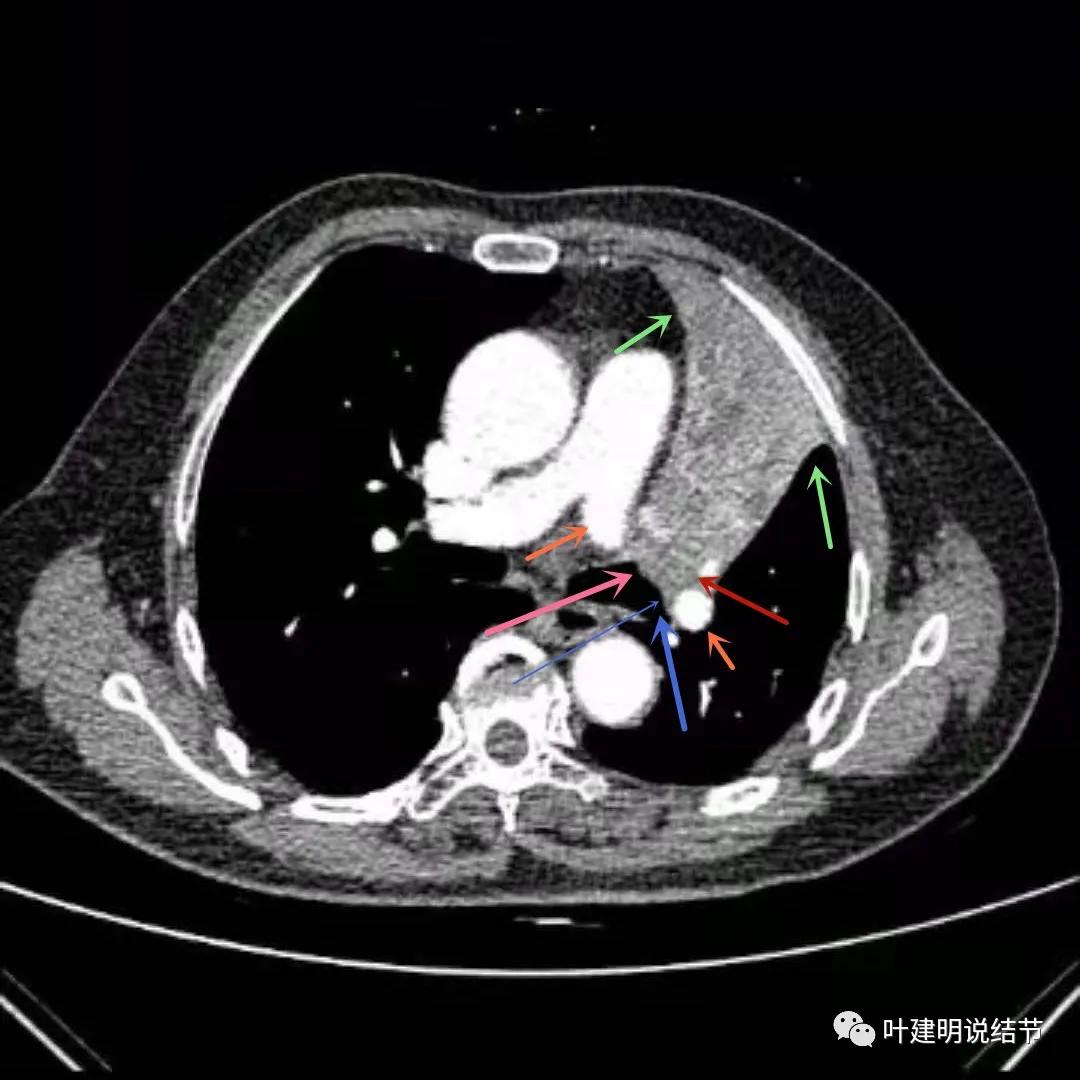

上图绿色箭头所指区域考虑不张的肺组织,红色箭头所指附近为肿瘤,且有膨胀性

上图绿色箭头所指区域考虑为肺不张,红色示肿瘤处,桔色箭头所指处是被肿瘤包绕的肺动脉分支

上图绿色箭头所指区域考虑为肺不张,红色示肿瘤处且有不均质与膨胀性,桔色细箭头所指处是被肿瘤包绕的肺动脉分支起始部,粗桔色箭头示肺动脉与肿瘤间紧密愈着,考虑有侵犯肺动脉